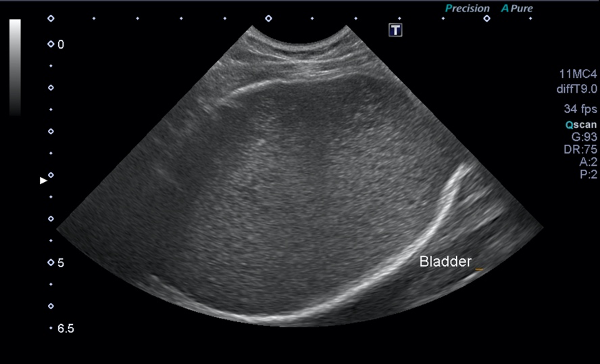

超音波検査で膀胱内に多量の尿が認められ、膀胱内の尿はモザイク様に観察されました。

超音波検査でも、膀胱内の尿が綺麗になっているのが確認できます。